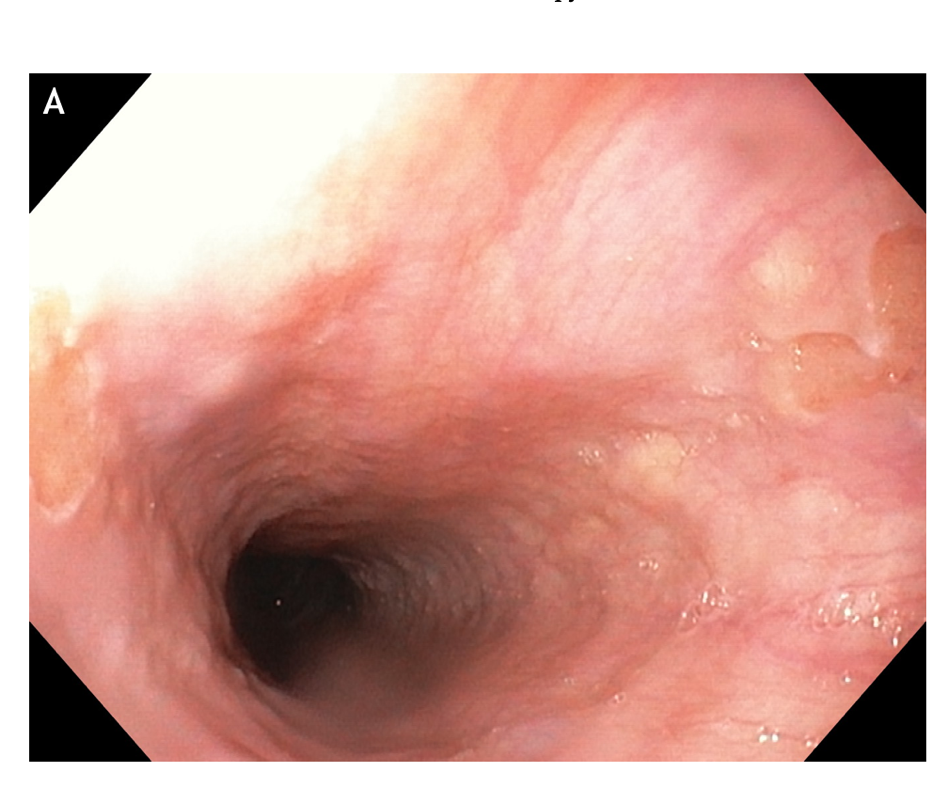

Figure 1 A discreet area of flat salmon pink mucosa with mucus on surface typically found in the proximal esophagus of a 45-year-old anxious woman with globus sensation.